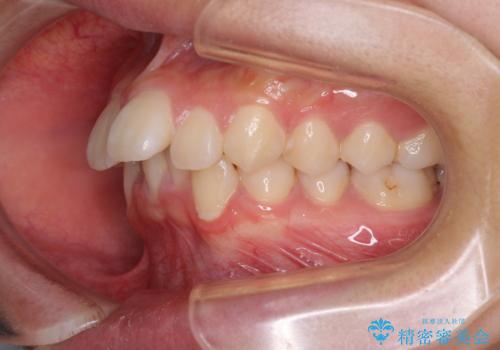

- 前に傾斜して飛び出した上顎前歯を気にして来院された患者様です。

上下前歯の前後差が大きく、下顎前歯が隠れるほど深い咬合で、咬合力が強い状態でした。

深い咬み合わせの改善に時間がかかりましたが、下顎前歯がしっかりと見えるまでに整えることができ、口元の突出感も大幅に改善することができました。